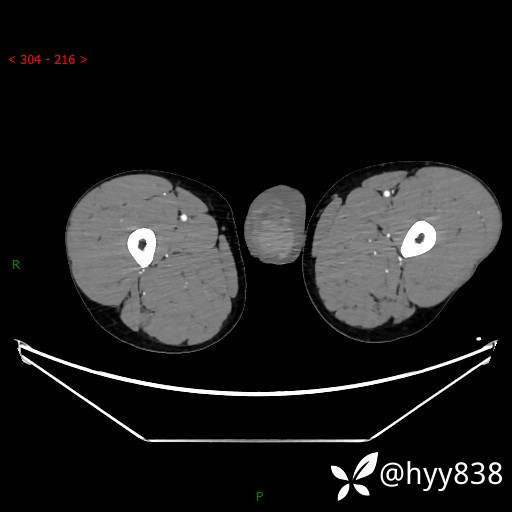

静脉期